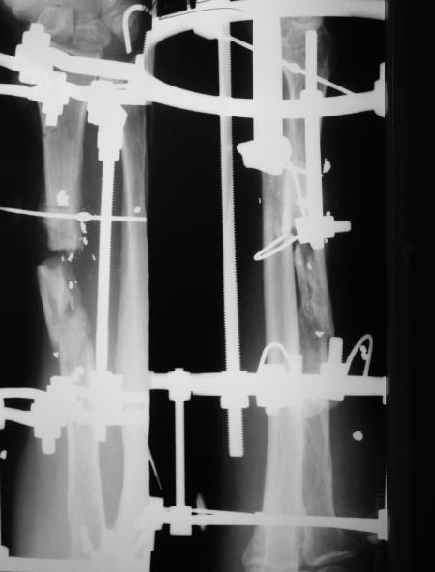

В приложении - снимок по окончании дистракции, и после смены аппарата на стержень (довольно толстый, 5 мм). С входом в канал на центральном отломке пришлось малость попотеть, промежуточный отломок его прикрывал. Но все-таки удалось закрыто проколупать. Надеюсь, дня через 3-4 после операции можно будет передать пациента нейрохирургам. Буду признателен за критику и комментарии.

Все за и про интрамедуллярной фиксации этого перелома луча уже обсуждались - все идет по плану.

Твоя концепция стабилизации отломков, своего рода *протезирования* лучевой кости продемонстрирована на Ргграммах. Прямого кость-кость контакта между дистальным и промежуточным фрагментами не получилось, что может скомпрометировать сращение перелома, хотя при первично стабильной фиксации и сохраненной надкостнице можно рассчитывать не

формирование периостальной мозоли (видимо этот механизм и работал в твоих прежних случаях).